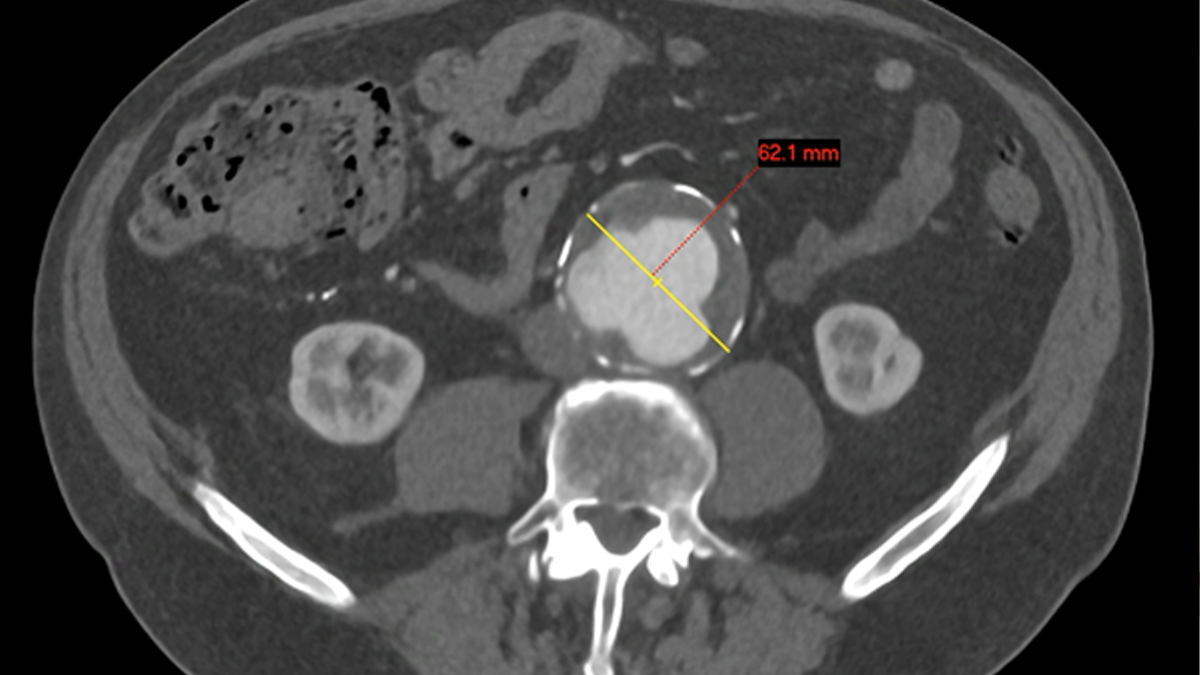

Aortic Aneurysm (AAA)

• Screening

• Surveillance

• Treatment

• Open Surgery

• EVAR

• Complex EVAR ( FEVAR,BEVAR, TEVAR)